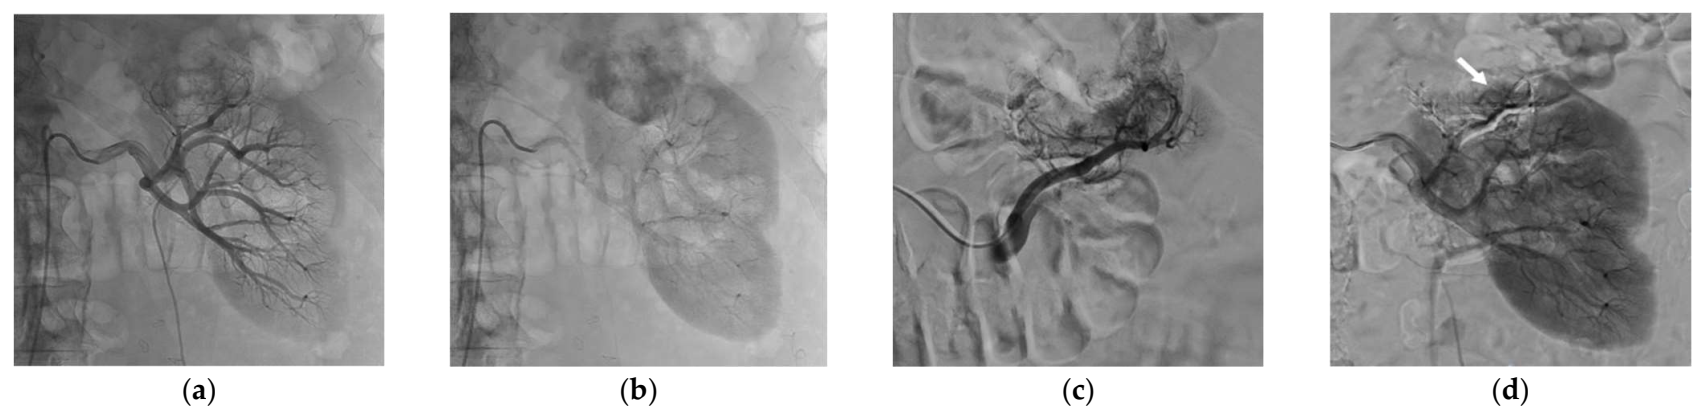

Successful SAE was achieved for all patients, but complete SAE in 11 patients (57.9%). Complete SAE could not be achieved in the remaining eight patients since it would have led to an unacceptable loss of surrounding healthy tissue. However, for cases with incomplete embolization, devascularization was obtained for most of the tumor volume, always greater than 50% on control angiogram. The most used NBCA/Lipiodol® ratio range was 1/3 to 1/5, in 18 patients. Mean procedure time was 93 ± 43 min and mean fluoroscopy time was 18 ± 11 min. The mean DSP for the SAE procedure was 120.7 ± 68.7 Gy.cm2. The mean volume of injected contrast medium was 119 ± 50 mL. The mean NRS pain score was 0.89 ± 1.52 after SAE. Table 3 lists the main characteristics of the SAE procedure. Figure 1 and Figure 2 show examples of SAE of renal cell carcinoma before PCA.

Figure 1.

Selective arterial embolization (SAE) procedure using NBCA/Lipiodol® mixture performed before percutaneous cryoablation of a renal cell carcinoma of the left kidney. (a) Angiogram showed hypervascularization of the renal malignancy with one feeding artery. (b) Control angiogram after SAE using NBCA/Lipiodol® mixture (1/5 ratio) showing the complete occlusion of the tumor vessels and devascularization of the tumor whereas the surrounding healthy tissue was spared.